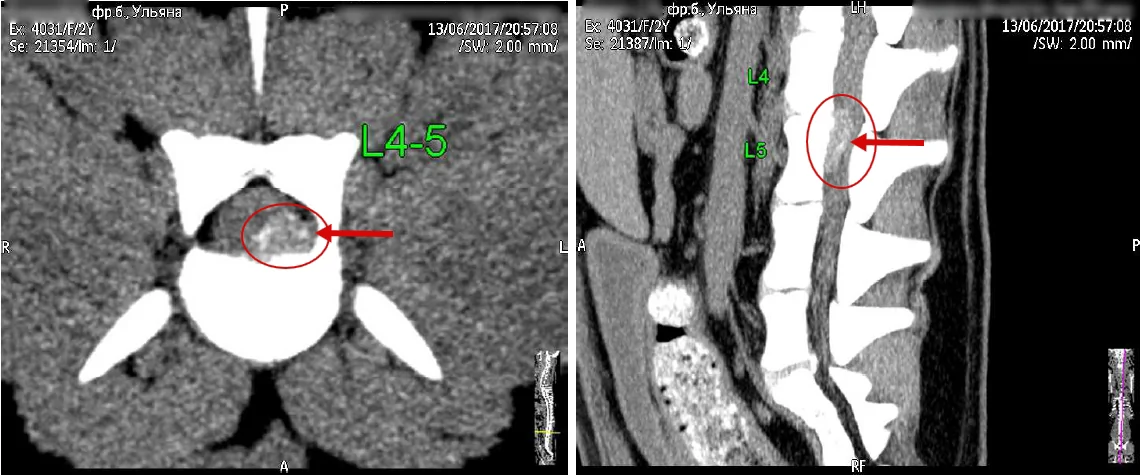

Дискоспондилит — частое заболевание в ветеринарной практике, но достаточно трудно диагностируемое на начальном этапе развития болезни. Зачастую ветеринарные врачи при диагностике путают его со спондилёзом, хотя оно имеет свои отличительные особенности в клинической картине и диагностике. Диагностика дискоспондилита должна включать помимо общего и неврологического осмотра специальные методы исследования, такие как рентгенологическое исследование, МРТ и КТ.

В дифференциальной диагностике помимо спондилёза должны учитываться онкологические болезни позвоночника — опухоли тел позвонков. Отличительная особенность новообразований позвонков — это интактность границ диска и поражения в пределах одного позвонка.

Рис. 1. Дискоспондилит у собаки при КТ диагностике.

При рентгенографическом исследовании характерными признаками дискоспондилита будут являться сужение межпозвонковых пространств, деминерализация иэрозированиесубхондральных пластинок, неравномерность замыкательных пластинок, разрастание костной ткани с образованием спондилофитов, вплоть досращения позвонков. Может наблюдаться расширение межпозвонкового пространства и эрозия тел позвонков.

Компьютерная томография — более подробное исследование костной ткани, признаки будут те же, как при рентгенографической диагностике.

Магнитно-резонансная томография при дискоспондилите позволяет увидеть заболевание на раннем этапе развития. При МРТ можно определить вовлеченность в процесс воспаления спинного мозга, увидеть компрессионные проблемы и, соответственно, более детально оценить патологический процесс. Характерными признаками на МРТ в режиме Т-1 являются понижение мр-сигнала от диска и прилежащей к диску части тела позвонка. В режиме Т-2- повышение мр-сигнала от этих структур.